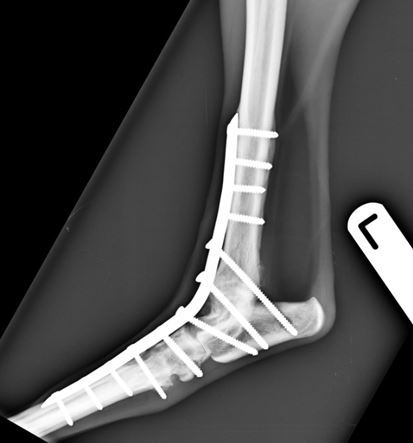

Six-weeks following surgery radiographs revealed excellent progression of arthrodesis and no evidence of implant associated problems. Normal exercise was gradually re-introduced at this point. Pantarsal arthrodesis was successful for salvaging a pain-free hindlimb after a potentially catastrophic fracture of the articular surface of the talus of a greyhound.

Figure 3. Six-weeks post-operative lateral view